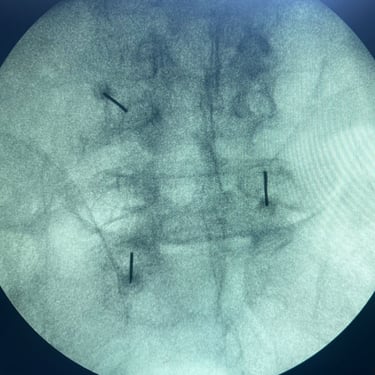

La lumbalgia crónica es una causa frecuente de dolor e incapacidad en el adulto mayor, generalmente asociada a degeneración discal, artrosis facetaria o compresión nerviosa. Cuando el dolor persiste pese al tratamiento convencional, se recurre al bloqueo lumbar selectivo, un procedimiento mínimamente invasivo que consiste en inyectar anestésico y antiinflamatorio alrededor de la raíz nerviosa afectada. Este tratamiento permite identificar el origen del dolor y aliviarlo de manera rápida y efectiva, mejorando la movilidad y calidad de vida del paciente. Es una alternativa segura, ambulatoria y con excelentes resultados en el manejo del dolor lumbar crónico.